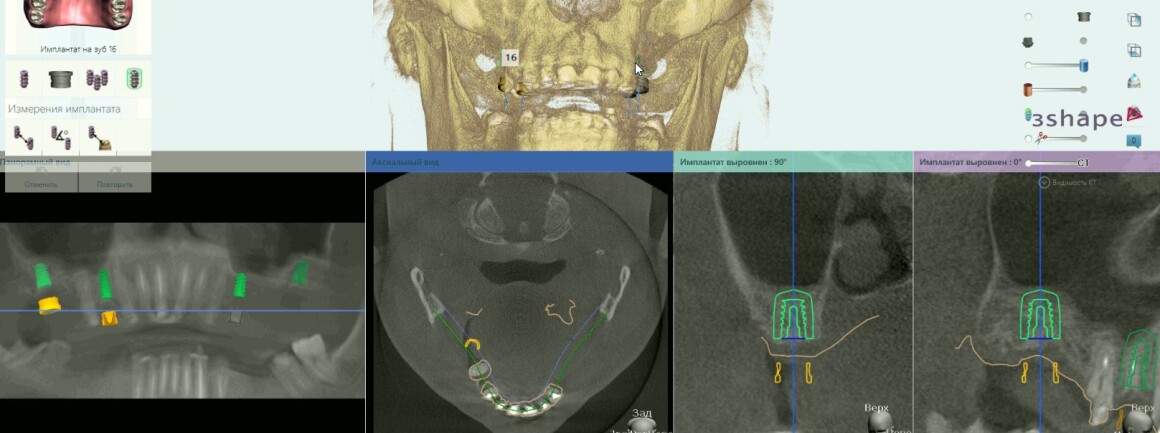

• Планирование имплантации

• Изготовление шаблонов для операции

• Имплантация 12 имплантантов за один раз